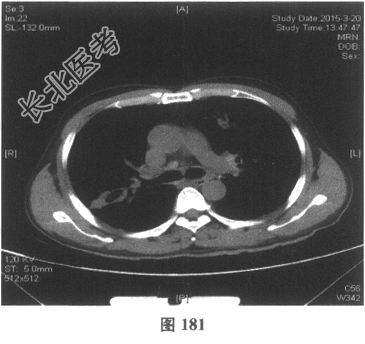

- [材料题] 患者男性,52岁,因间断发热伴咳嗽,咳少许黄痰,无咯血,伴胸闷憋气20余天就诊。体检:体温37.6~38.3℃。既往体健。查体:体温37.6℃,心率83次/分,呼吸20次/分,血压117/64mmHg。神志清,精神可,口唇无发绀;双肺呼吸音粗,可闻及广泛干、湿性啰音,以干啰音为主;心率83次/分,律齐,各瓣膜听诊区未闻及病理性杂音;腹软,无压痛及反跳痛,肠鸣音3次/分,双下肢无水肿。血常规检查:白细胞计数26.32×109/L,中性粒细胞0.846,血红蛋白117g/L,血小板计数1911×109/L;C反应蛋白119.05mg/L。尿常规检查:隐血2(+),蛋白1(+)。痰培养:曲霉菌属,请排除污染。生化全套检查:白蛋白19.6g/L,谷丙转氨酶24.2U/L,谷草转氨酶25.8U/L,γ-谷氨酰基转移酶91.4U/L;尿素氮13.00mmol/L(2.14~7.14mmol/L),肌酐166.8μmol/L(31~132μmol/L);血钾5.6mmol/L。肺部CT见图178~图185。

- 多项选择题4.[提示]患者应用多种抗生素治疗(第三代头孢菌素、青霉素加酶抑制剂)包括抗曲霉菌治疗无效,加用甲泼尼龙40mg静脉滴注病情好转。肺部CT检查显示病变明显改善。尿常规检查正常, 肾功能检测正常。复查肺部CT(图188~图195):示病变较前好转。Wegener肉芽肿的主要临床表现是( )